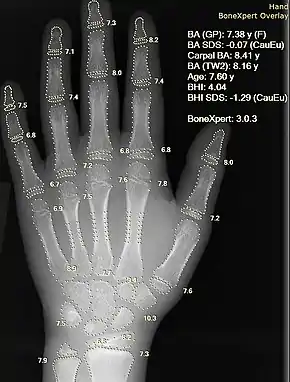

بیمارستانها و دارو

شبکه عصبی مصنوعی به عنوان سیستم پشتیبانی بالینی تصمیمی برای تشخیص پزشکی استفاده میشود، مانند تکنولوژی پردازش مفهوم در نرمافزار EMR.

- تفسیر کامپیوتری از تصاویر پزشکی. چنین سیستمی به اسکن تصاویر دیجیتالی، از جمله از طریق توموگرافی رایانه ای، برای نمایشهای معمول و به منظور برجسته بخشهای قابل توجه مانند بیماریهای ممکن است. یک برنامه معمول تشخیص تومور است.